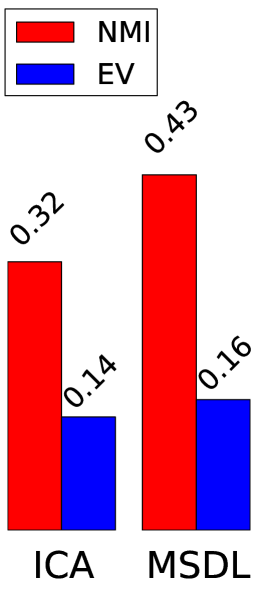

To quantify the usefulness of a set of regions extracted automatically, we consider metrics that characterize two different aspects of the segmentation: the ability to explain newly observed data and the reproducibility of the information extracted, as in the NPAIRS framework [7]. We use Explained Variance (EV) to measure how faithful the extracted regions are to unseen data. Stability with regards to inter-subject variability is measured using Normalized Mutual Information (NMI) over models learned on disjoint subsets of subjects.

Figure 2 presents region extraction results using each method on the same map. In all figures, the threshold applied during region extraction is shown in a given slice to help understanding. Results for each metric are displayed on the right. We vary parameters for each model (smoothing for ICA, 3 parameters of MSDL) and, for each region extraction method, display the best 10% results across parametrization. Figure 4 shows 2 networks out of 42 extracted.

Stability.

Random Walker dominates the stability metric. It uses local maxima to get regions seeds, and will thus split regions even if they are connected after thresholding. Its performance is statistically significant for both dense and sparse atlases and any parametrization. The stability improvement is larger for sparse than for dense maps. This could be due to the inability of random walker to compensate for the original instabilities of the models.

Data fidelity.

Starting from hard thresholding [2], we introduce richer strategies integrating spatial models, to avoid small spurious regions and isolate each salient feature in a dedicated region. Indeed, the notion of regions is hard to express with convex penalties. Relaxations such as total-variation used in [1] only captures it partially, while a non-convex segmentation step easily enforces regions. We find that a Random-Walker based strategy brings substantial increase in stability of the regions extracted, while keeping very good explanatory power on unseen data. Finer results and interpretation may arise by using more adapted metrics, for example a version of DICE that can deal with overlapping fuzzy regions. This point is under investigation.